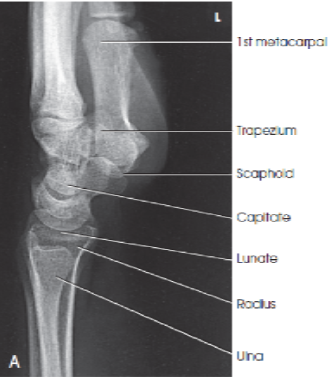

What are the structures shown in a PA oblique wrist image?

A

distal radius and ulna, carpals, and proximal half of metacarpals (lateral metacarpals)

-

45 degree rotation of anatomy

slight overlap of the distal radius and ulna

slight interosseous space between third, fourth, and fifth metacarpal bodies

trapezium and distal half of the scaphoid without superimposition